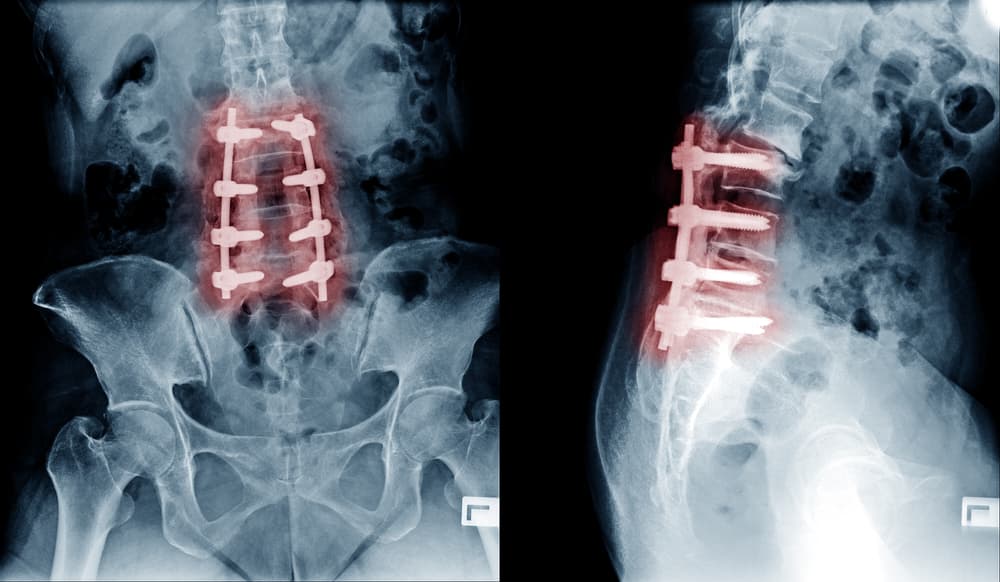

Spinal Fusion Surgery: why it might not fix your lower back pain

Back pain: Australia spends almost $5 billion on treatments for it every year, and yet it’s still one of the main reasons for GP visits. Spinal Fusion Surgery is among several therapies out there that your doctor might recommend- but it’s caused much disagreement in the surgical community due to limited evidence for its effectiveness. Nic chatted to Ian Harris, Professor in Orthopaedic Surgery at UNSW, about what the surgery is, what medical conditions might prompt it, and why its use is increasing.